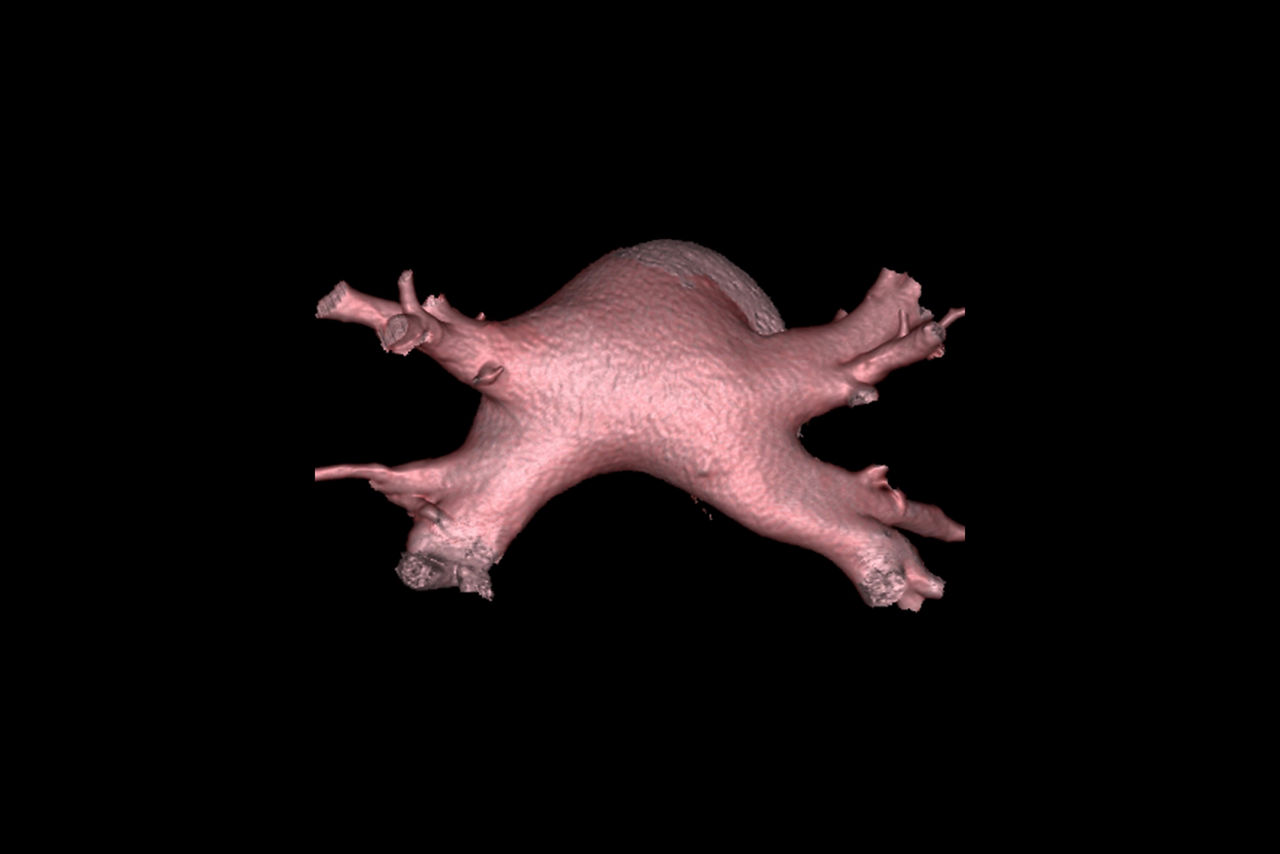

Automatic heart segmentation

Visualize the anatomical layout of the left atrium and pulmonary vessels and the origins of the pulmonary vessels

Coronary sinus and pulmonary vein analysis

Visualize and quantify cardiac venous pathways